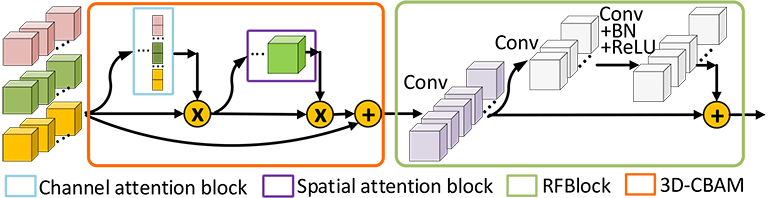

Inspired by attention mechanism, we propose 3D-CBAM, which is an attention framework specifically designed for 3D multi-modality medical images, to recalibrate multi-source features to reduce confusion when fusing them. It uses a channel attention block and a spatial attention block to highlight both informative features and ROIs. For the design of channel attention block, in order to provide more sufficient information for 3D medical images, besides max-values and average-values, standard deviations (stds) are also captured to make final channel-wise weights. Meanwhile, stds are also adopted to improve the performance of spatial channel block. Additionally, we respectively set three MLPs for these three kinds of features due to the huge differences among the distribution of average-values, max-values and stds.

As illustrated in Figure 2, our framework is an end-to-end fully convolutional network, containing three encoders to take 3D images from three modalities of MRI as inputs. The encoder network is a VGG-liked [34] DNN, which stacks base block containing several 3D convolutional layers followed by max-pooling layers to get deeper features. And the decoder network uses 3D deconvolutional layers to upsample feature maps, the final output is a feature map with the same size as input. Both low-level features and high-level features, which are relevant to NPC segmentation, can be obtained by the design of multiple encoders and one single decoder. In order to effectively fuse low-level features from multi-modality MRI and keep balance between high-level and low-level features, a fusion block composed with 3D-CBAM and RFBlock is proposed to recalibrate and fuse multi-source low-level feature maps. For the training of network, we propose self-transfer to use pre-trained modality-specific encoders, which can capture individual modality-specific features from single modality MRI, as initial encoders of multi-modality model. The utilization of self-transfer can effectively improve the performance of encoders and make full mining of informative features from every modality of data.

The purpose of fusion block is to effectively recalibrate and fuse low-level features from different modalities of MRI before merging them with high-level features. It is a hard task to directly fuse low-level features from multiple MRI, which vary greatly from each other due to the varied responses to different tissues of multi-modality MRI. Therefore, the fusion block will firstly re-weighting features and highlight regions that are greatly relevant to NPC with the assistance of 3D-CBAM. 3D-CBAM is composed with a channel attention block, which focuses on ’what’ are meaningful features, and a spatial attention block, which focuses on ‘where’ is an interesting part. After recalibrating low-level features, an RFBlock is utilized to fuse them into ones with the same channel number of corresponding high-level features to keep balance between them. The architectures of them are shown in Figure 4.

Channel attention block. The focus of channel attention block is to selectively emphasize feature maps, which are meaningful for final predictions. SENet [31] utilizes global average pooling to capture average-values of each feature map, and feeds them into a MLP to get weights for every channel. Compared to SENet, the channel attention block of CBAM [32] uses global max-pooling layers to get max-values of feature maps in additional to capturing average-values using global average-pooling layers. And both average-values and max-values are fed into a shared MLP. Then, the output vectors are combined by add operation.

Spatial attention block. The purpose of spatial attention block is to utilize feature maps after channel-wise refining to obtain 3D spatial attention map (). On the basis of previous work of CBAM, we capture stds, average-values and max-values along the channel axis and concatenate them to generate three 3D feature blocks. And these features are fed into a 3D convolutional layer with sigmoid as activation to produce . Through element-wise multiplication, informative regions will be effectively highlighted. The architecture of spatial attention block is shown in Figure 4(b), and the process can be summarized as followed:

Residual fusion block. After highlighting informative features and ROIs, a residual fusion block is constructed to fuse and refine low-level features. It is worth mentioning that the numbers of channels are for , while the corresponding high-level features, which is prepared to combine with fused features, only has channels. Therefore, in order to keep balance between low-level and high-level features, an convolutional layer with channel outputs is utilized to fuse feature maps and reduce channel number firstly. Then, a residual block [39] is adopted to refine feature maps. This block is composed with two convolutional layers, both of them have kernels and the first one is followed by a batch normalization layer and a ReLU layer. We can summary this process using following equations: